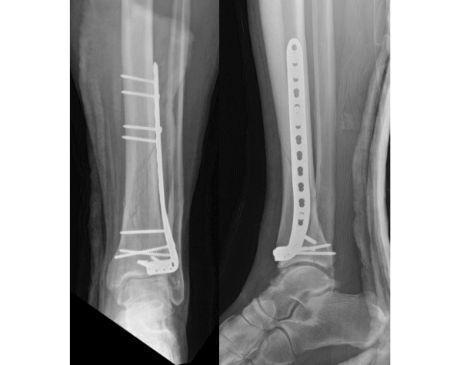

I was hit by car, had a compound fracture with a bone sticking out of my left foot. Broken tibia and fibia?. Screwed plate and bones back together. I am healing fine, next visit 3/26 to remove stiches. I seem to have total function of foot. Still have 2 more weeks of not using leg, but very hopeful.